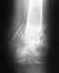

Здравствуйте дорогие травматологи-ортопеды!Помогите определиться с дальнейшим лечением.Внутрисуставной перелом локтевого сустава 8.07.2019операция 15.07.в сентябре рекомендовали снять гипс и разрабатывать локоть. в результате всё развалилось

• Кликните для загрузки файла Doc3.docx